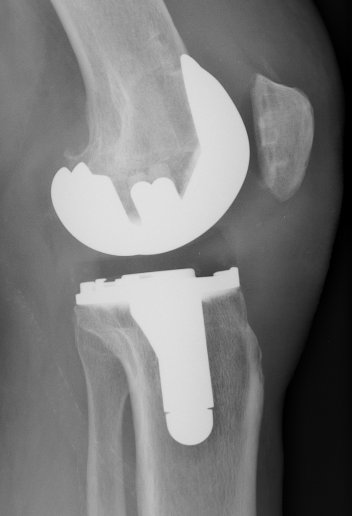

B. PTG à glissement avec quille d'extension tibiale

quille d’extension tibiale.

patients en surpoids ou ostéoporose